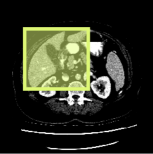

Consider a three-dimensional object within a volume. It is straightforward to produce a 3D bounding box of the object by finding its extreme points in the three coordinate axes. While this 3D bounding box will be tight in the 3D sense, its rectangular cross-sections will not, in general, remain tight with respect to the planar cross-sections of the volume. Fig. 1 illustrates such a case for the task of liver segmentation in a CT volume. In the Experiments section we show that the success of existing 2D weakly-supervised segmentation methods relies on the bounding boxes being tight and therefore the tightness of the individual 2D bounding boxes should be corrected before training and applying a segmentation CNN.

(a)

(b)

(c)

(d)

The global bounding box tightness prior mentioned above assumes that each of side of the box is sufficiently close to the target region. This means that for any region shape, each vertical or horizontal line inside the bounding box will cross at least one pixel belonging to the target region. This condition does not hold when the provided annotation comes as a 3D bounding box which is represented as a series of per-slice non-tight 2D bounding boxes. In this case, there will exist vertical or horizontal lines shown as stripes in Fig. 1 (d), that will lie outside of the actual object boundary. In the Experiments section we demonstrate the poor performance of the weakly-supervised approach from [5] when the user-provided bounding box is much wider than the true object of interest.